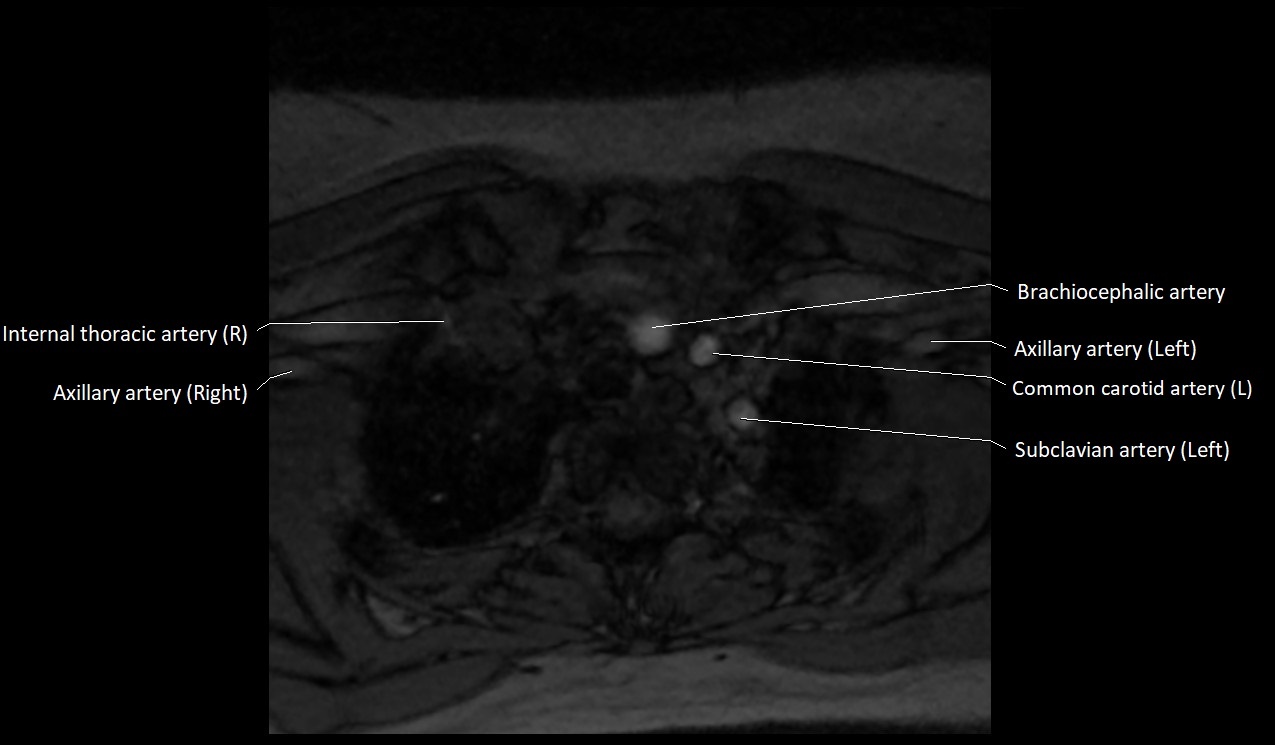

MRI images

image